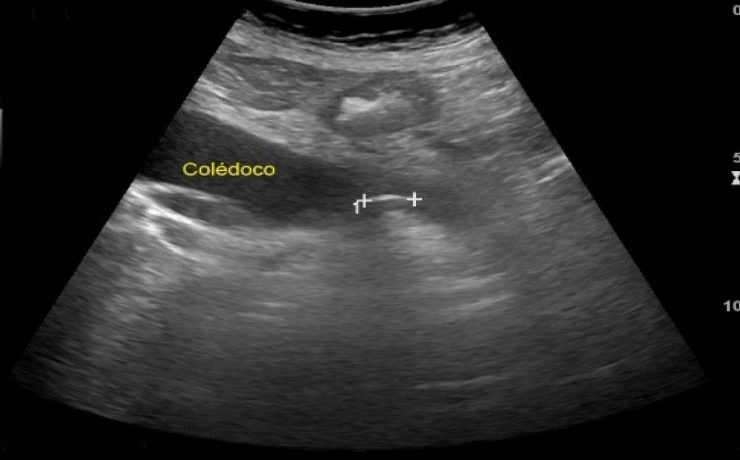

Utilidad del ultrasonido en el abordaje quirúrgico del hígado

El hígado es la más voluminosa de las vísceras y una de las más importantes por su actividad metabólica. Es un órgano glandular al que se adjudica funciones muy importantes, tales como la síntesis de proteínas plasmáticas, función desintoxicante, almacenaje de vitaminas y glucógeno, además